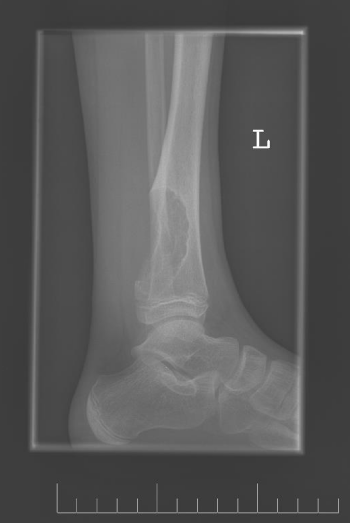

A 10-year-old female presented with left lower leg pain that had progressively increased over the duration of 1 year. On physical examination, tenderness was elicited on palpation of the distal tibia. Routine laboratory testing was normal. X-Ray was performed and revealed a lytic lesion with sclerotic margins in the left lower tibia (Figure 1). MRI was subsequently performed, demonstrating a left lower tibia lesion with low signal intensity on T1 weighted images (Figure 2), and high signal intensity on T2 weighted images (Figure 3). Pathology of the tumor revealed a diagnosis of a CMF. She was treated with curettage and autologous bone grafting (Figure 4). Post op eratively the left leg was immobilized with a plaster cast with restricted weight bearing (Figure 5). Follow up X-ray after 5 years demonstrates no tumor reoccurrence (Figure 6, Figure 7).

Figure 1: Initial lateral X-ray of the left ankle.

Imaging is crucial to the diagnosis of this tumor. On X-ray the tumor appears as a space occupying radiolucent osteolytic lesion with sharp and well-defined margins (Figure 1). The margins are noted to be sclerotic (Figure 8) the tumor has no soft tissue component (Figure 9). There is no matrix calcification or visible periosteal reaction (Figure 10).